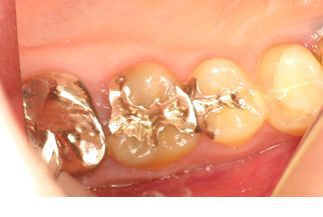

マイクロスコープによる原因歯の特定

問診・視診・打診・温度診・レントゲンなどの検査を行っても原因が特定できない場合でも、マイクロスコープで検査を行うことで何が原因になっているか特定できる症例はたくさんあります。